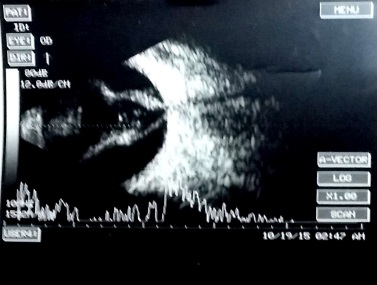

[The funnel RD is attached to the disc and is not showing after-movements with ocular movements.]

In cases of bullous retinal detachments with 'shifting fluid' (in sitting position the RD is inferior bullous and superior retina seems attached; in supine position, there is a total retinal detachment), it may be necessary to rule out an exudative retinal detachment (ERD). ERD usually shows subretinal echoe. A choroidal mass may be detectable, or the ultrasound may reveal another cause of the ERD (e.g., posterior scleritis, Vogt-Koyanagi-Harada syndrome).